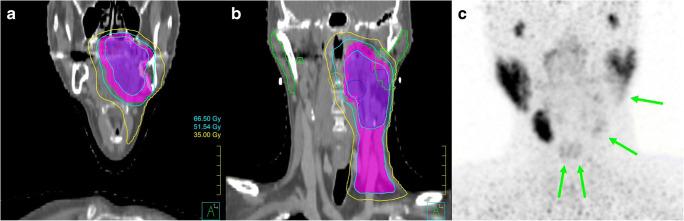

Radiation therapy is an effective treatment modality for a variety of cancers. Despite several advances in delivery techniques, its main drawback remains the deposition of dose in normal tissues which can result in toxicity. Common practices of evaluating toxicity, using questionnaires and grading systems, provide little underlying information beyond subjective scores, and this can limit further optimization of treatment strategies. Nuclear medicine imaging techniques can be utilised to directly measure regional baseline function and function loss from internal/external radiation therapy within normal tissues in an in vivo setting with high spatial resolution. This can be correlated with dose delivered by radiotherapy techniques to establish objective dose-effect relationships, and can also be used in the treatment planning step to spare normal tissues more efficiently. Toxicity in radionuclide therapy typically occurs due to undesired off-target uptake in normal tissues. Molecular imaging using diagnostic analogues of therapeutic radionuclides can be used to test various interventional protective strategies that can potentially reduce this normal tissue uptake without compromising tumour uptake. We provide an overview of the existing literature on these applications of nuclear medicine imaging in diverse normal tissue types utilising various tracers, and discuss its future potential.